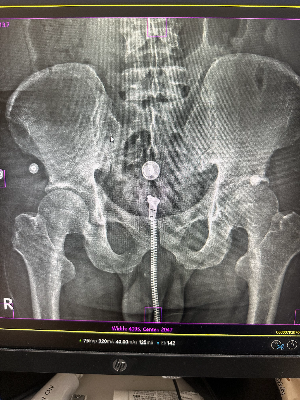

③ 등산복, 청바지의 금속 단추와 지퍼

어르신들이 즐겨 입으시는 등산복이나 아웃도어 의류에는 크고 작은 쇠단추와 쇠지퍼가 수십 개씩 달려있습니다. 청바지 역시 두꺼운 재봉선과 금속 징이 박혀있죠. 허리나 골반, 무릎 사진을 찍을 때 이 옷들을 그대로 입고 찍는다면, 관절염의 정도를 확인해야 할 뼈 사이의 간격을 지퍼가 다 가려버리는 불상사가 발생합니다.

A. 촬영 부위에 따라 다릅니다. 가슴(흉부) 엑스레이를 찍을 때 하의 주머니에 있는 물건은 가슴 사진 영역에 들어오지 않으므로 굳이 빼실 필요가 없습니다. 하지만 허리나 골반, 고관절 엑스레이를 찍을 때는 주머니 속의 스마트폰, 열쇠, 동전이 골반뼈를 완벽하게 가려버리므로 반드시 모두 비워주셔야 합니다.